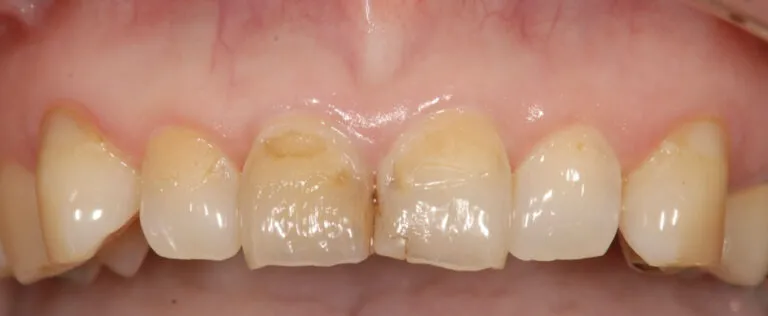

症例4

- 主訴

- 前歯が痛い。全体的な治療を希望

- 治療内容

- インプラント治療、矯正治療、セラミックによる補綴治療

- 治療費

- 400万

- 治療期間

- 2年3ヶ月

- 通院回数

- 70回

before

after